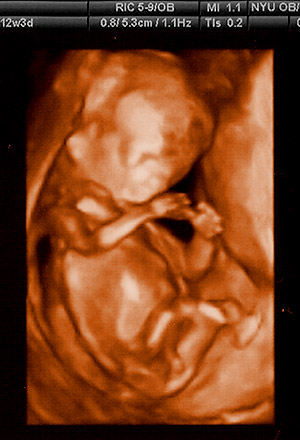

Month 3 (Week 12)

The baby loses its tail, moves on from the embryo stage and is now called a fetus. The fetus measures about 6.5 to 7.5 cm (2.5 to 3 inches) and starts to move on its own, but you usually can't feel these movements yet. The umbilical cord has formed by this month and the placenta starts functioning. The sex organs of the baby begin to differentiate. Your doctor may be able to hear the baby's heartbeat with special instruments.